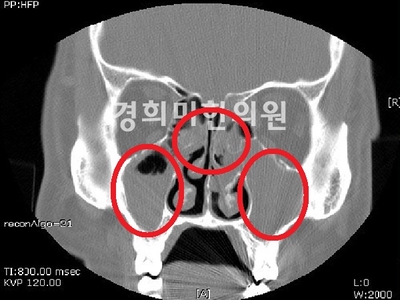

부비강염 CT영상

편도염, 만약 급성 비염의 카탈기가 지나 2차 세균 감염이 되면 진한 황색의 콧물과 함께 코막힘, 뒷코 막힘이 심해집니다.더욱 심해지면 부비강염, 중이염, 인두편도염, 기관지염, 폐렴, 장염 등 다양한 합병증을 동반할 수 있습니다.이러한 합병증은 면역력이 떨어진 환자나 어린이에게서 자주 나타나므로 주의가 필요합니다.